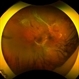

- Mike Mackens

- Imaging device

- Fundus camera

- Severe traction retinal detachment with diabetic retinopathy